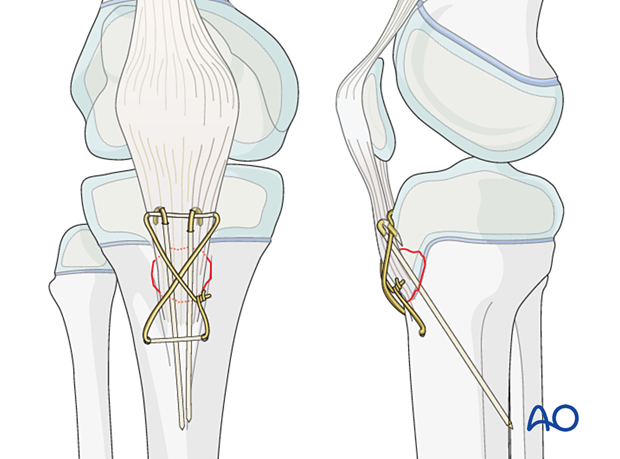

Loss of Fixation of a Type IV Supracondylar Humerus Fracture。Type 4 Tibial Tuberosity Avulsion Fractures: Surgical。Spinal Trauma Specific Injuries - OrthoPaedia。イタリア出身のデスメタル/エクストリームメタルバンドNERVEが2013年に発表した3rdアルバム『Fracture』輸入盤デジパックディスク無音部に少し傷がありますが再生には問題ありません。。